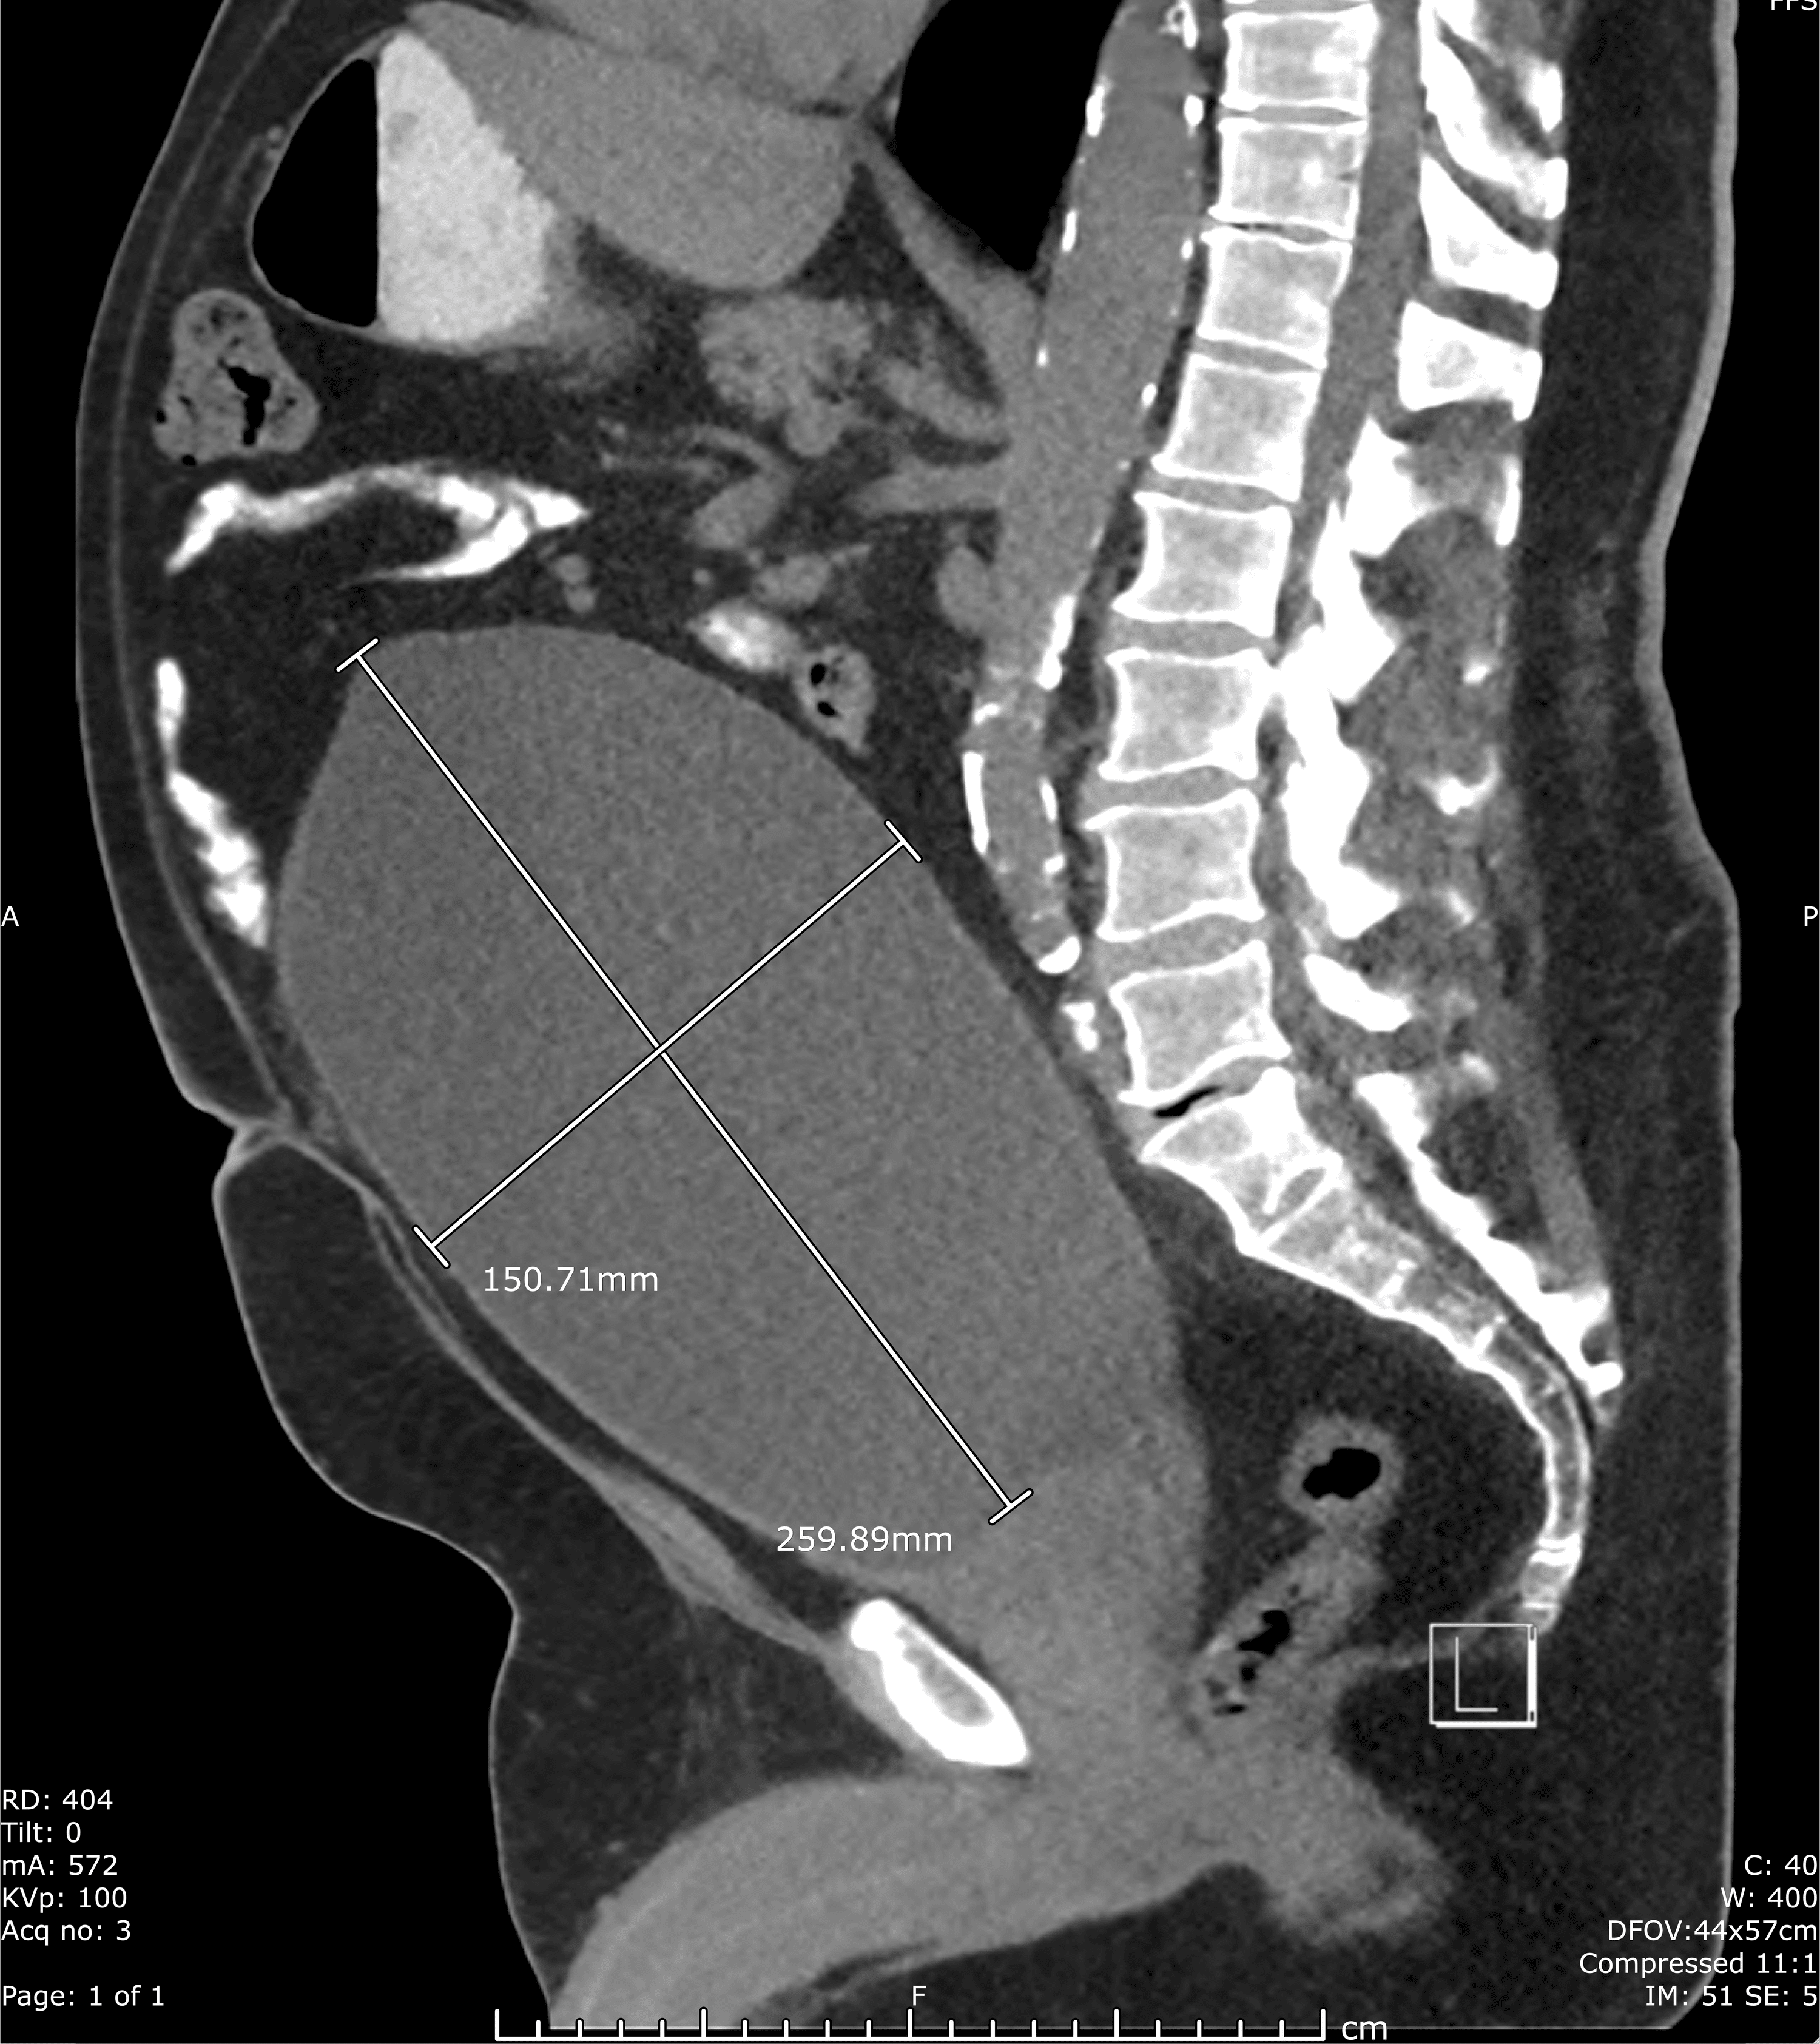

Cureus Severe Urinary Retention Resulting in Extreme Postobstructive Does Urine Retention Cause Stomach Pain — urinary retention is difficulty completely emptying the bladder. It can be acute or chronic and may be. It can be acute or chronic and affect both males and. in severe cases, it can cause digestive discomfort and lower abdominal pain. urinary retention can be acute—a sudden inability to urinate, or chronic—a gradual inability to completely empty. Does Urine Retention Cause Stomach Pain.

Cureus Severe Urinary Retention Resulting in Extreme Postobstructive Does Urine Retention Cause Stomach Pain — urinary retention is the inability to empty the bladder completely. Find out how to measure postvoid. learn about the causes, diagnosis, and treatment of urinary retention, the inability to voluntarily pass urine. — urinary retention is when you are unable to empty your bladder completely. — urinary retention is when your bladder doesn’t empty completely.. Does Urine Retention Cause Stomach Pain.